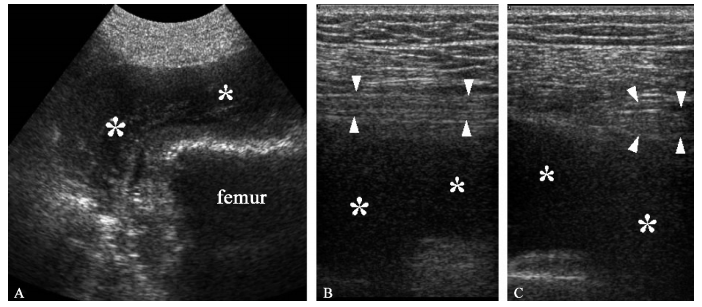

A. 髋关节后方12~4MHz超声矢状继面显示断髋关节置换术后发生的一个部分性大血肿(* )。坐骨神经12~5MHz超声矢状断面(B)和短轴断面(C)显示在积血(* )部位坐骨神经移位和受牵拉(箭头端)然而,检查者应该意识到超声对于探查这么深区域的轻微病变敏感性较低,尤其是肥胖患者;对于显示近端的梨状肌处的病变和坐骨大孔处的病变亦不敏感。尤其梨状肌综合征时由于坐骨神经在坐骨大切迹处被压引起下背部及坐骨神经痛,超声亦不能显示,因为神经走行于臀肌深面,位置很深。同样的,对于梨状肌肥大及其他异常超声也难以提供可靠的信息。因此,MRI在准确诊断梨状肌综合征及与其他可能造成下腰部疼痛的原因进行鉴别的方面优于超声。

坐骨切迹远端,大多数坐骨神经的病变源自严重的创伤,比如髋关节骨折脱位,或并发于髋关节置换术,其他原因包括长时间卧床制动、腘绳肌综合征愈合时坐骨结节区域瘢痕形成、撕脱的骨碎片直接撞击神经、占位性病变及梨状肌综合征。临床上,坐骨神经完全损伤可导致腘绳肌及膝以下肌肉瘫痪,胫、腓神经所支配的皮肤感觉缺失。一般来说,坐骨神经外侧干更易受累,导致假性腓总神经病变。全髋关节置换术的患者,小腿拉长超过4cm,术中髋关节脱位,局部出血及牵引器的直接损伤均可导致神经损伤。临床表现包括臀部向大腿放射的疼痛及步行能力减弱。这时,超声可以显示局部神经的病变及瘢痕组织和血肿对神经的压迫(图 一)。